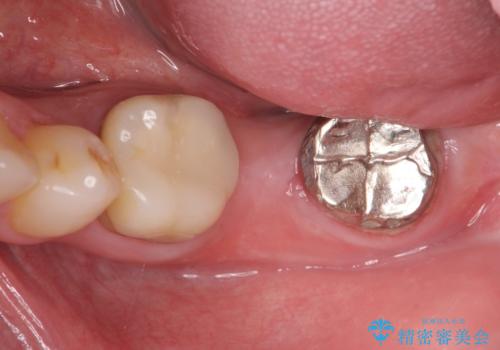

最後方臼歯のインプラント補綴

最後方臼歯の治療について

最後方臼歯を喪失した場合、入れ歯・インプラントによる咬合機能回復方法があります。

今回はしっかりと噛むことができ、取り外しの必要のないインプラントによる補綴を行いました。